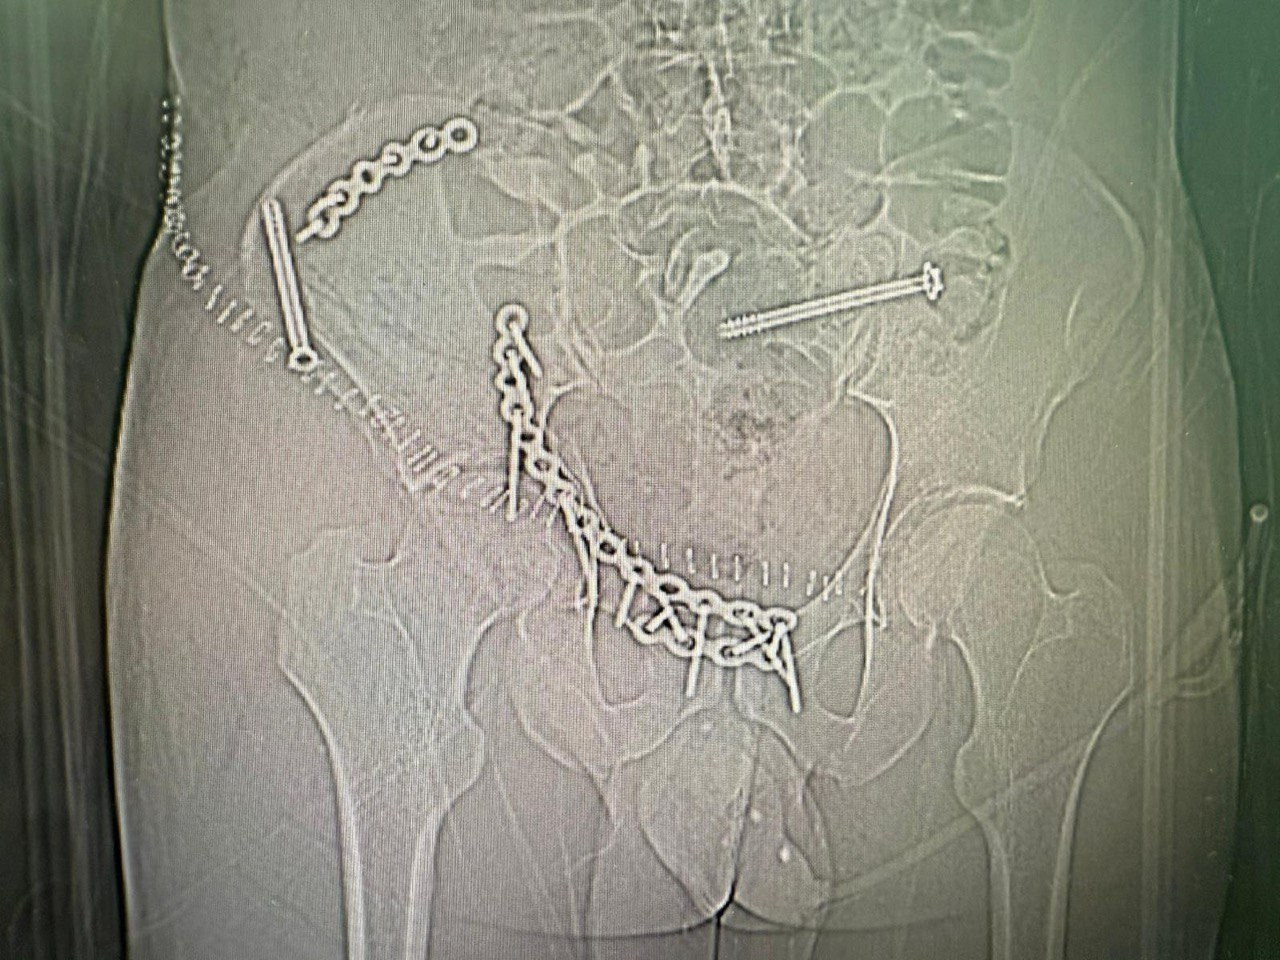

He sustained multiple fractures that required immediate and highly complex surgical treatment. Good news - legs sensitivity is still there. Bad news - he got L4 L5 compression fracture, shattered hip/pelvis and a broken nose. He has already undergone two very complex surgeries for hip reconstruction, one minor nose surgery and now he have to be bed bound for at least 6 weeks under medical supervision.

Hip surgeries were difficult. They required transfering Fedor to a different city to find the only doctor that can do it. A lot of luck that they were a success! But that was not cheap.